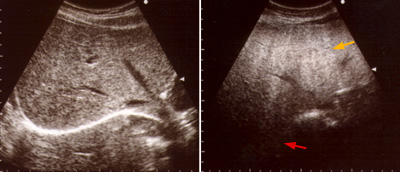

A demonstração do acúmulo de gordura geralmente é realizada através de exames complementares de imagem (ecografia, tomografia computadorizada ou ressonância nuclear magnética). Estes exames são considerados geralmente suficientes para o diagnóstico da esteatose, podendo também informar se há sinais de desenvolvimento de cirrose ou de hipertensão portal. Mas não permitem a diferenciação entre a esteatose e a esteato-hepatite nem diferenciar graus intermediários de fibrose ou de atividade da inflamação. É possível diferenciar grosseiramente o acúmulo de gordura entre leve (grau I), moderada (grau II) e severa (grau III), embora isso tenha pouca utilidade clínica.

No entanto os exames de imagem, especialmente a ultrassonografia, podem errar o diagnóstico. Doenças como a hemocromatose (onde há acúmulo de ferro no fígado) e glicogenoses (acúmulo de metabólitos de glicogênio) podem ser muito semelhantes à esteatose. Assim, considera-se que o melhor exame para o diagnóstico da esteatose é a biópsia hepática com análise histopatológica do material coletado. Além de confirmar a presença do acúmulo de gordura e diferenciar de outras doenças, permite avaliar se há hepatite e o quanto a doença está avançada em termos de fibrose.